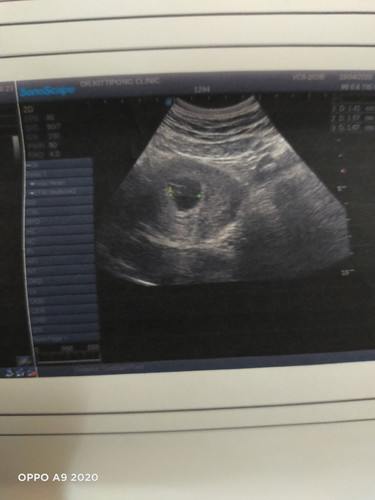

เคลียมาก็เลยต้นเเือนไปซาวก็เจอเเต่ถุงตั้งครรภ์ วันที่18ไปซาวก็เจอเเต่ถุงตั้งครรภ์ หมอนัดวันที่2เดือนน่าให้ไปซาวอีก1รอบ กลัวท้องลม